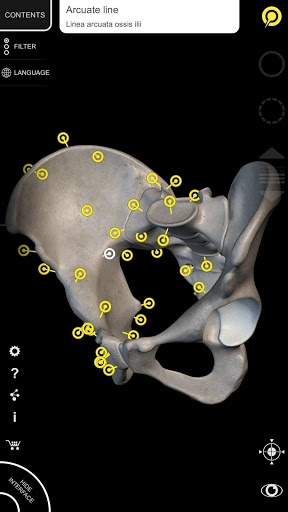

يتيح لك "Anatomy 3D Atlas" دراسة التشريح البشري بطريقة سهلة وتفاعلية.

من خلال واجهة بسيطة وبديهية، من الممكن ملاحظة كل بنية تشريحية من أي زاوية.

تتميز النماذج التشريحية ثلاثية الأبعاد بتفاصيل خاصة ودقة تصل إلى 4K.

يسهل التقسيم حسب المناطق والمناظر المحددة مسبقًا مراقبة ودراسة الأجزاء الفردية أو مجموعات الأنظمة والعلاقات بين الأعضاء المختلفة.

نماذج تشريحية ثلاثية الأبعاد

• الجهاز العضلي الهيكلي